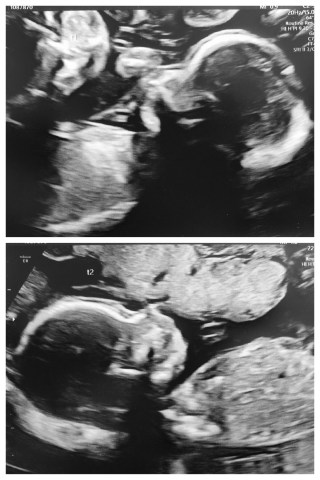

He really struggled to get me some decent photos of them because of how they were laying, however, to his credit he really persevered and managed to get some images that look like babies!

They started off the scan both head down next to each other, twin one on the left and twin two on the right.

He was very thorough and checked all their major organs, their faces and spines, and double checked for me that they were both boys (definitely)